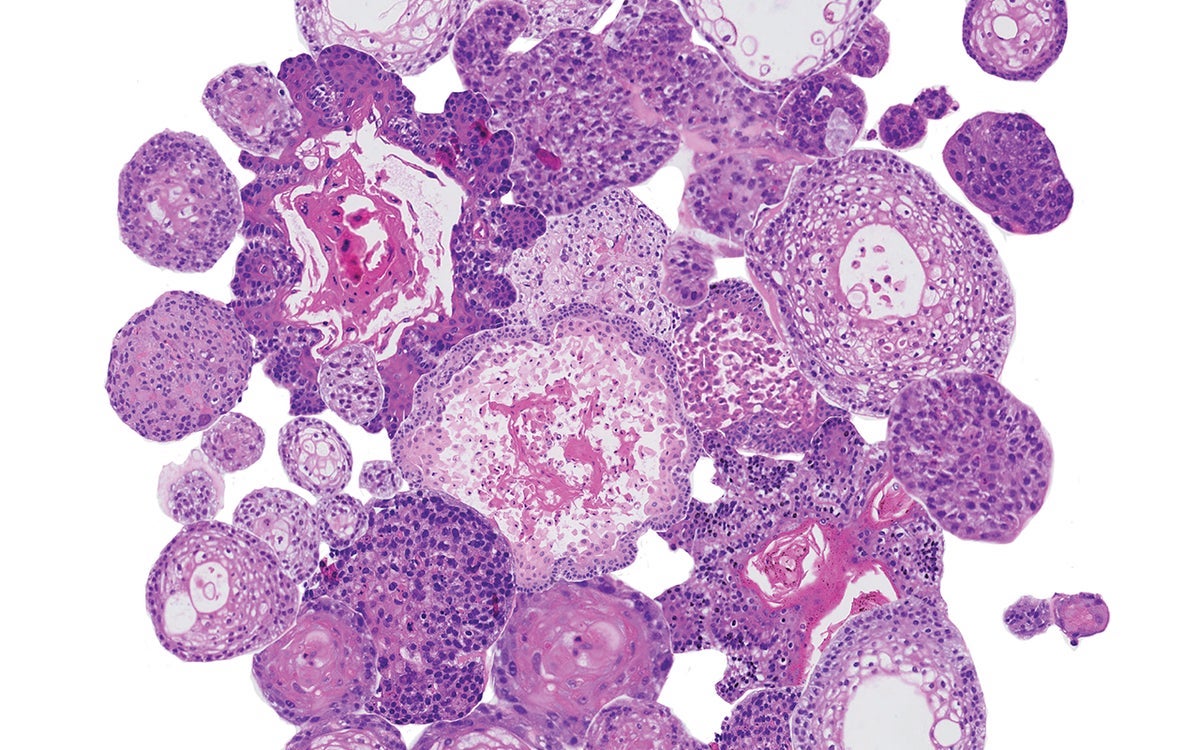

Onder hoofd-halskanker verstaan we alle kwaadaardige tumoren van de bovenste lucht- en voedselwegen. De belangrijkste locaties zijn de mondholte, de keelholte, het strottenhoofd, de speekselklieren en de neus- en neusbijholten.

Er zijn verschillende soorten hoofd-halskanker, maar ze hebben veel overeenkomsten. Bijvoorbeeld in de manier waarop zij ontstaan en de manier waarop zij uitzaaien. Ook zijn er overeenkomsten in hoe we de ziekte opsporen (de methoden van diagnostisch onderzoek), behandeling en revalidatie.